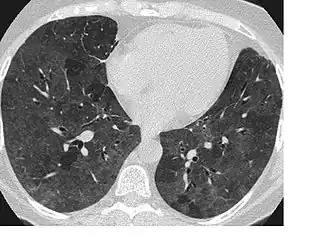

![]() КТ-картина экзогенного аллергического альвеолита с облитетирующим бронхиолитом («воздушные ловушки») | |

- Компьютерная томография высокого разрешения демонстрирует мозаичную воздушность лёгочной ткани за счёт наличия «воздушных ловушек». Наиболее достоверно данные изменения выявляются при исследовании в фазе глубокого выдоха.